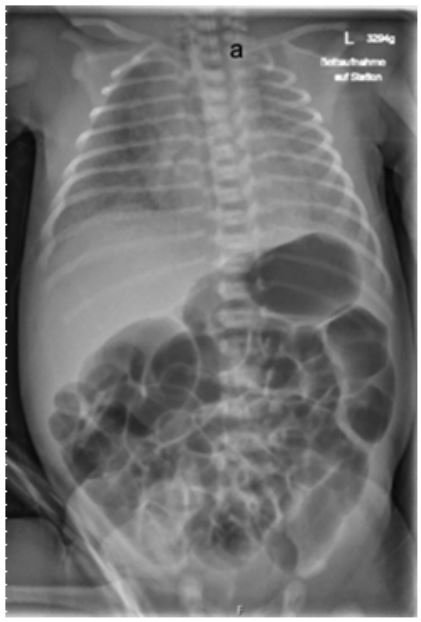

Figure 1: Posterior-anterior X-ray of thorax on admission. High-placed gastric tube lying in the blind sac in case of esophageal atresia (a). Blown-up intestinal loops as an indication of tracheoesophageal fistula.

The delivery was performed at 37 completed weeks of gestation via Cesarean section due to velamentous insertion. The neonate was postnatally vital, with APGAR scores of 7/8/9 and birth weight of 3295 grams (64th percentile). Immediately after birth the infant exhibited respiratory distress and an increased oxygen requirement, necessitating the initiation of CPAP- therapy. Placement of a gastric tube was not feasible, and an X-ray revealed an esophageal blind pouch (Figure 1).